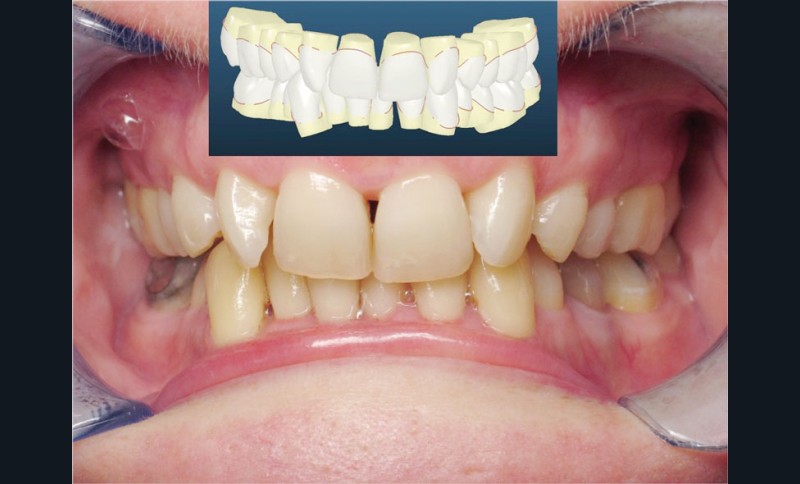

Cas n° 2

Nous lui avons donc proposé un traitement d’alignement avec maintien des 14 et 24 en position de 13 et 23 et optimisation du torque pour favoriser un développement des arcades et chercher à améliorer le sourire et le soutien labial.

La patiente donne son accord pour un appareillage Damon Insignia métal qui permet une individualisation complète des brackets dans les 3 sens de l’espace.